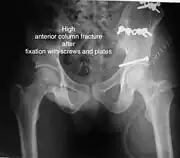

High anterior column fracture after fixation with screws and plates